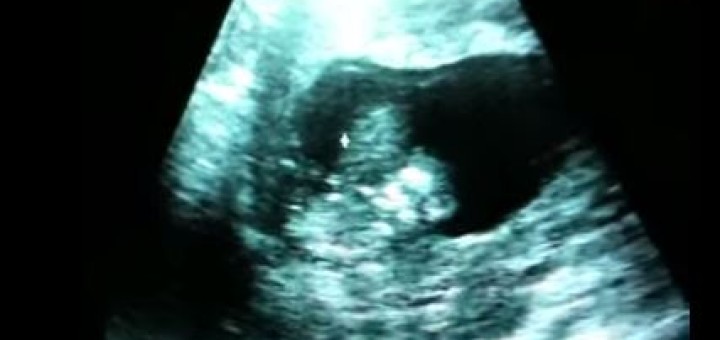

Mãe vê bebê a divertir-se no ventre através do Ultrasom/Ecografia

As ecografias (ultrasom) são feitas durante a gravidez pelas mais diversas razões todas elas ligadas à saúde do bebê. Mas se há coisa que qualquer mãe pretende da ecografia é conseguir ver o seu...